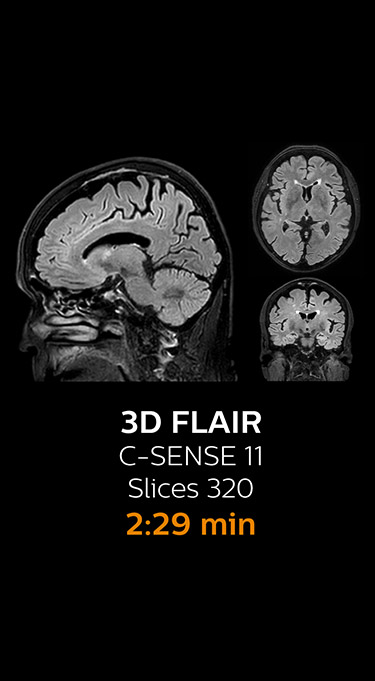

The most frequently used brain MRI examination at KNC included approximately 15 minutes of scanning time, and was quite comprehensive with fairly short scan times. When Compressed SENSE became available, its great impact on the brain exam quickly became clear.

Fast MRI of brain

With Compressed SENSE, the scan time for the routine brain examination at KNC was reduced from 15:48 to 10:19 minutes, which corresponds to 35% reduction.

Ingenia 3.0T CX

Scan time 15:48 min.

Brain with Compressed SENSE

Ingenia 3.0T CX

Scan time 10:19 min.